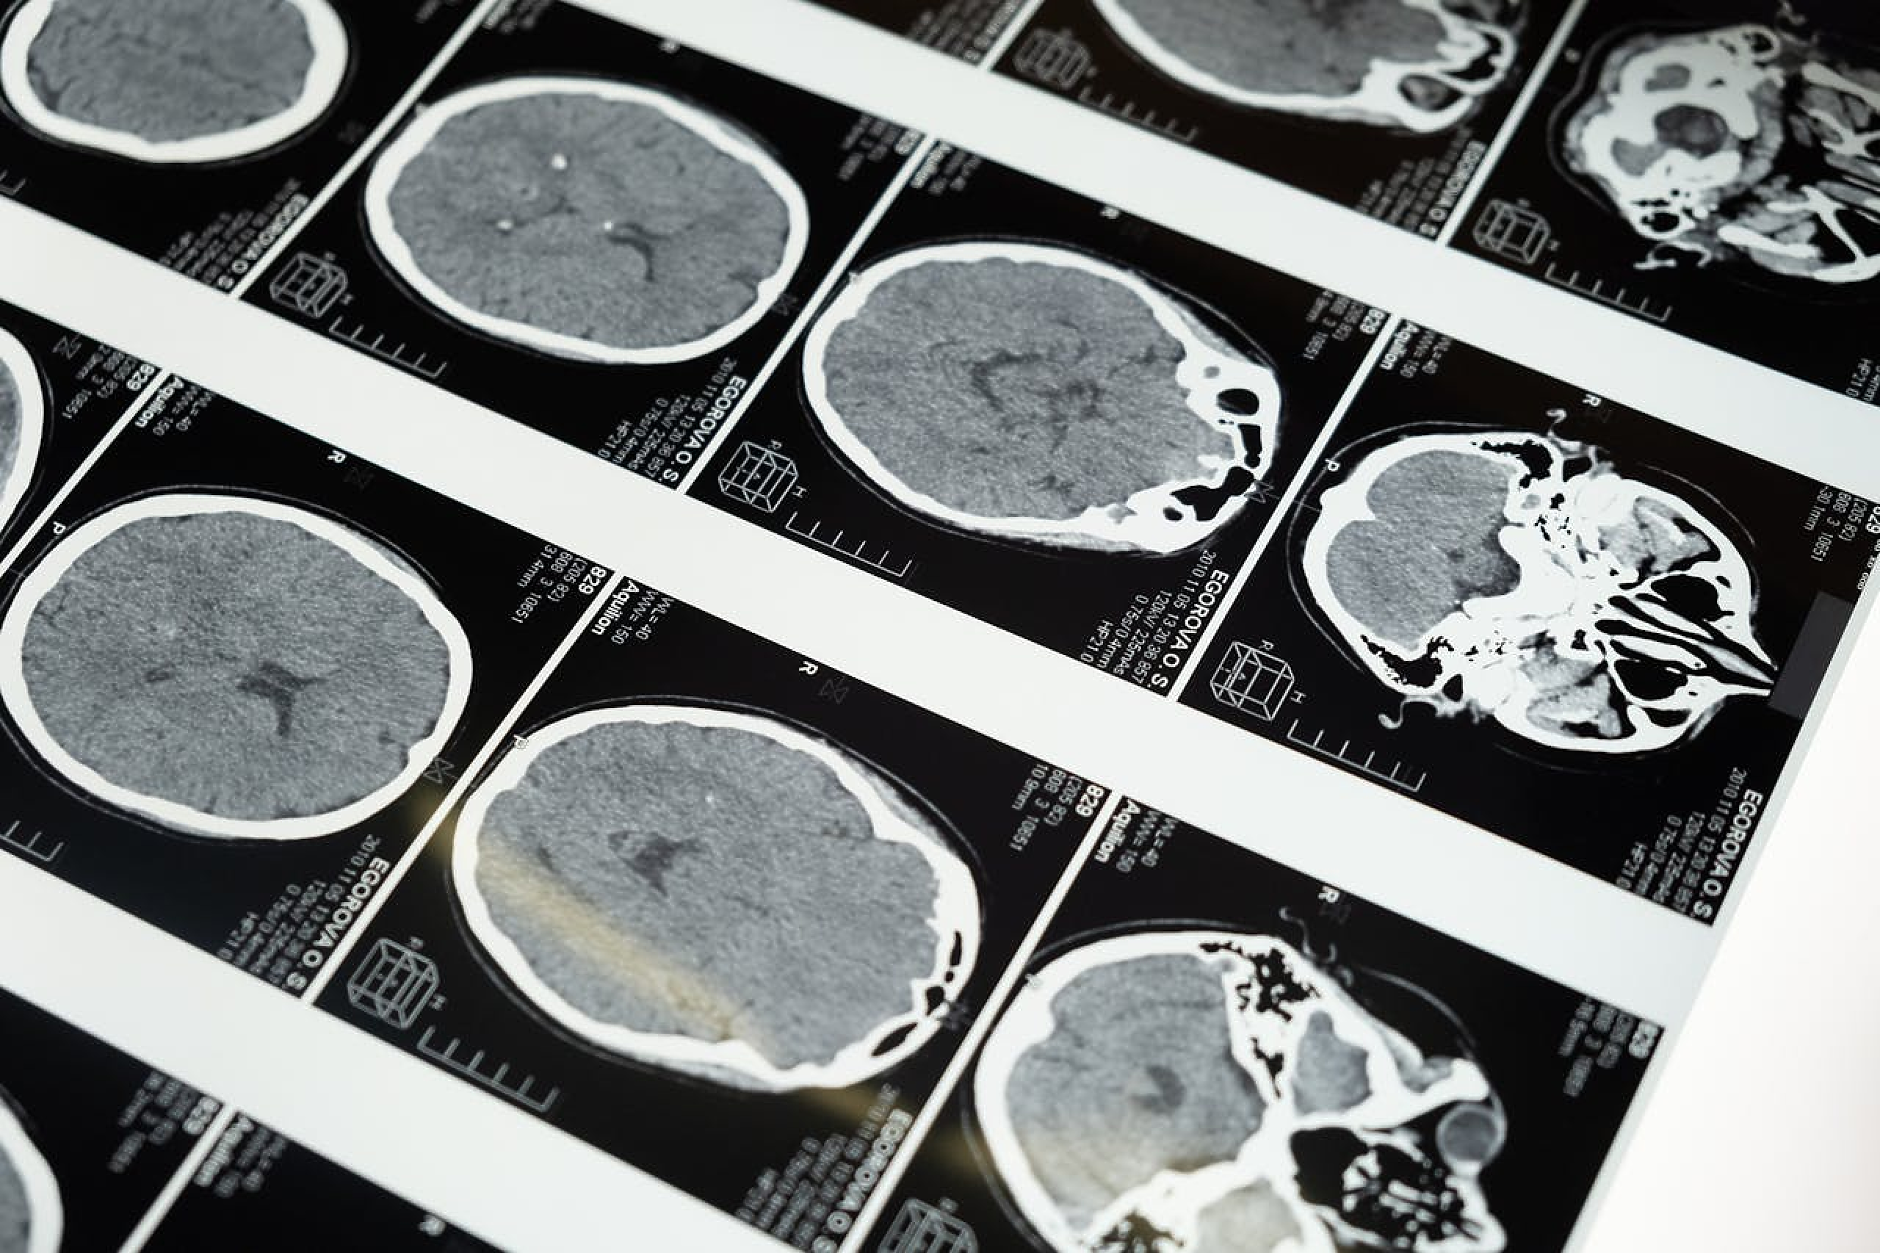

Проучването, базирано на мозъчни сканирания на близо 4000 души на възраст от под една година до 90 години, картографирало невронните връзки и тяхната еволюция през живота ни. Това разкрило пет широки фази, разделени от четири ключови „поворотни точки“, при които организацията на мозъка преминава към различна траектория – приблизително на 9, 32, 66 и 83 години.